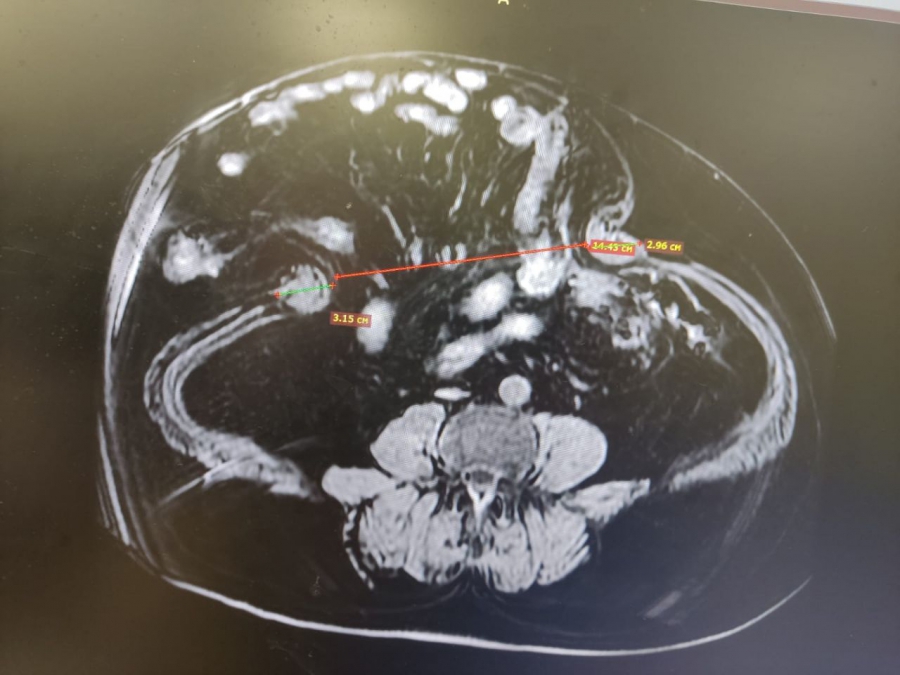

Помочь мужчине из Воронежа со сложной патологией взялись врачи больницы им. Фишера. В анамнезе пациента сахарный диабет и циркулярный инфаркт миокарда в 2021 году. Грыжа, диагностированная два года назад, увеличивалась в размерах, что сильно снижало качество жизни. Несмотря на возраст 65+, мужчина работает, ведет активный образ жизни.

Опираясь на результаты лабораторных и инструментальных методов диагностики пациента, врачи приняли решение о проведении оперативного лечения. Необходимо отметить, что при прохождении пациентом назначенных обследований выявлена желчекаменная болезнь, протекающая бессимптомно.

Симультанные — это операции, при которых во время одного оперативного вмешательства одновременно проводится до пяти различных хирургических манипуляций. Таким образом, в одно оперативное вмешательство пациенту сделали грыжесечение, холецистэктомию и заднюю сепарационную пластику передней брюшной стенки с использованием сетчатого импланта. Главное преимущество подобных операций – возможность уменьшить нагрузку на организм пациента, а также сокращение сроков лечения и восстановления.